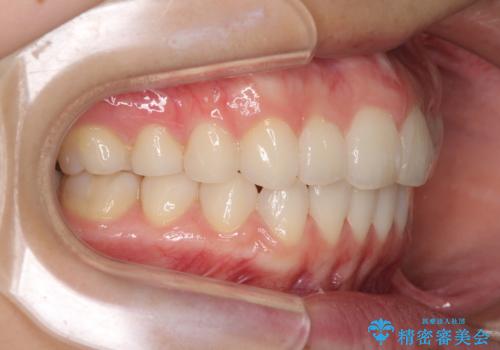

- デコボコと飛び出した前歯を治したいとのことで来院された患者様です。

ゴムかけを活用して上顎歯列全体を後方移動し、IPR(歯と歯の間を削る)によってデコボコが解消するように設計し、インビザラインにより治療を行うこととしました。

後方移動に際し、上下顎の親知らずは4本とも抜歯することとしました。

毎日しっかりと装着してくださったので、概ねシミュレーション通りに歯を移動させることができました。

治療前には接触することのなかった上下の前歯が接触するようになり、食事の際前歯でものをかみ切れるようになりました。

気にしていた口元の印象が改善され、患者様には大変満足していただきました。